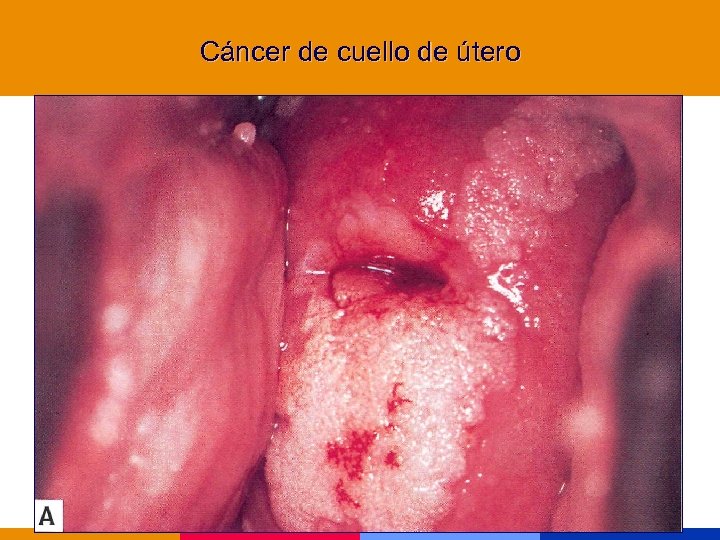

Categoría C (Enfermedades marcadoras) § Cáncer de cuello uterino, invasivo § Sarcoma de Kaposi § Linofoma no Hodking, primario de SNC

Categoría C (Enfermedades marcadoras) § Cáncer de cuello uterino, invasivo § Sarcoma de Kaposi § Linofoma no Hodking, primario de SNC

Neoplasias marcadoras § Cáncer de cuello uterino, invasivo § Sarcoma de Kaposi § Linofoma no Hodking, primario de SNC Incremento de otras neoplasias: pulmón, seminoma, melanoma, otras

Neoplasias marcadoras § Cáncer de cuello uterino, invasivo § Sarcoma de Kaposi § Linofoma no Hodking, primario de SNC Incremento de otras neoplasias: pulmón, seminoma, melanoma, otras

Cáncer de cuello de útero

Cáncer de cuello de útero